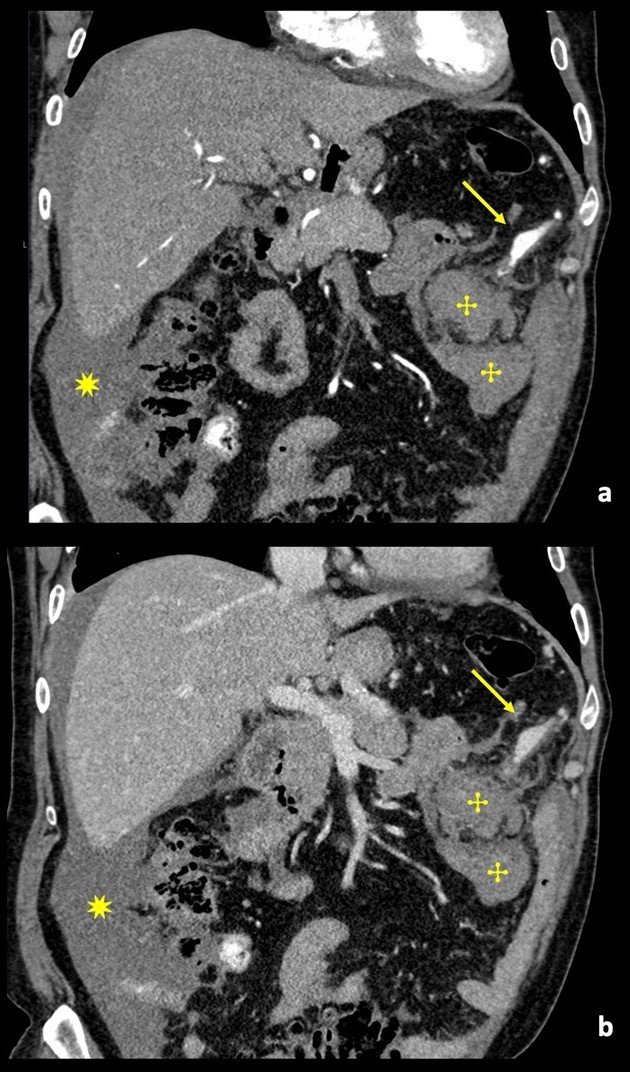

An enhanced CT of the abdomen showed high-density ascites with a moderate amount of blood and a hematoma on the left side of the omentum measuring approximately 5x5x4 cm in the longest axis in close proximity with a dilated and tortuous arterial branch of the gastroepiploic artery; there were no signs of active bleeding. The examination also revealed a fusiform dilatation of the celiac trunk (12mm of diameter). Additionally, the aorta displayed multiple atherosclerotic calcifications.(Fig. 1)

Figure 1: Contrast-enhanced coronal angio-CT reconstruction, in arterial phase (a) and venous phase (b), showing a multilobulated aneurysm sac (arrow) of the left gastroepiploic artery, without evidence of active hemorrhage. Adjacent to the aneurysmatic sac an intraperitoneal hematoma can be seen (✣). Hemoperitoneum (✷).